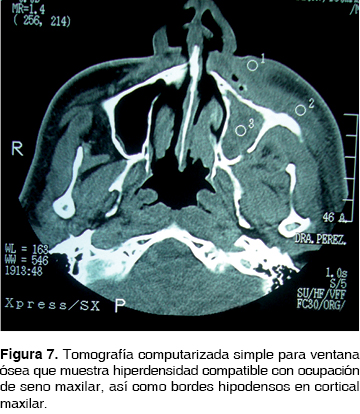

Masculino de 46 años de edad con antecedentes de diabetes mellitus tipo II descontrolada e hipertensión arterial sistémica de 15 años de evolución no controlada, el cual inicia su padecimiento 3 meses antes de la consulta refiriendo odontalgia en órgano dental maxilar y realizarse por sus propios medios la excéresis de dicho diente. Dos semanas posterior a este evento, inicia con sintomatología dolorosa en la región anterior maxilar, mal sabor de boca, halitosis. Evoluciona durante 3 meses con edema periorbitario, oclusión palpebral, fístula cutánea en ala nasal izquierda, intraoralmente con fístula en vestíbulo maxilar de 0.5 mm sin datos de salida de material purulento. Se le realiza tomografía computarizada donde se observan áreas líticas en el proceso ascendente del maxilar, y proceso maxilar del hueso malar, el seno maxilar se encuentra ocupado (Figura 7). En la biometría hemática presenta hemoglobina de 11.3 g/dL, leucocitos de 8.92 cpm, glucosa de 123 g/dL. Se inicia tratamiento farmacológico con clindamicina 600 mg IV cada 6 h y ceftriaxona 1 g IV cada 12 h. Posteriormente se realiza hemimaxilectomía subtotal respetando el reborde inferior orbitario bajo anestesia general inhalatoria balanceada, mediante abordaje circunvestibular de 5 cm con disección de tejidos hasta exposición ósea, observando áreas óseas de necrosis, se retira espécimen quirúrgico de 4.5 x 4 cm. Clínicamente se observan bordes óseos libres de lesión y se sutura con ácido poliglicólico 3 ceros.